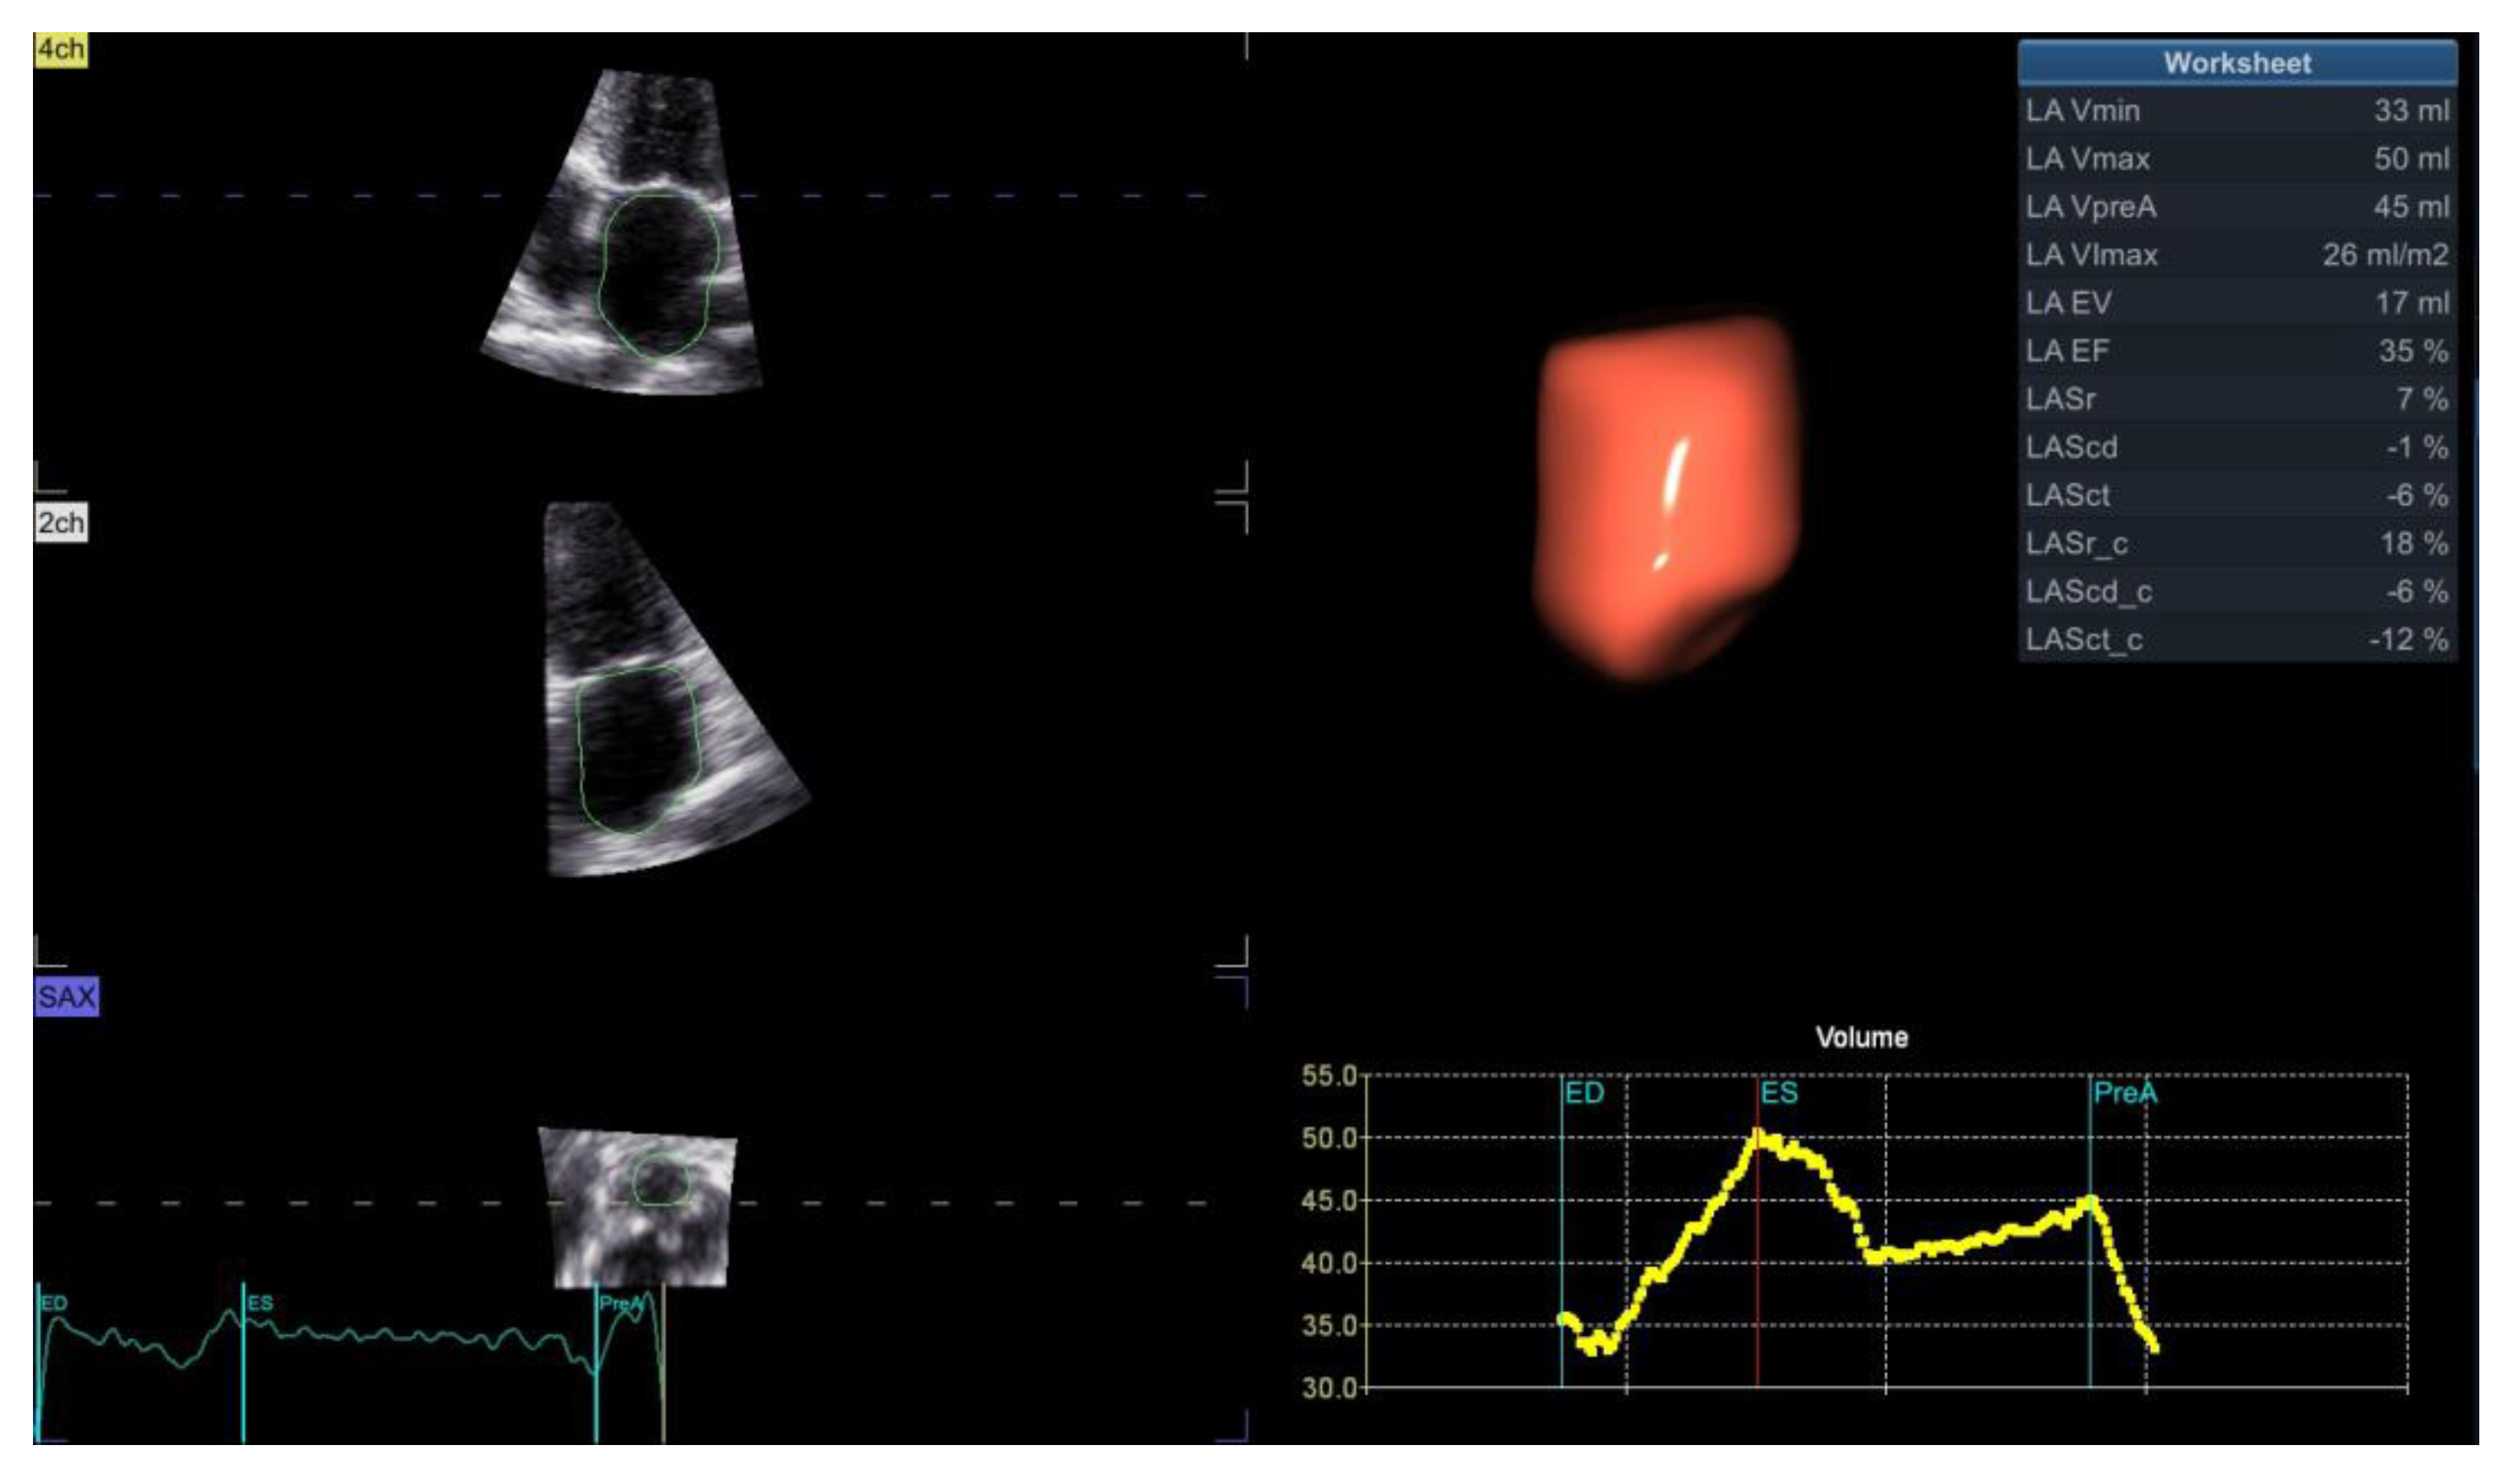

Based on the 3D atrial and ventricular volumes (Figure 1), we measured three atrioventricular coupling indices as follows: LACI, defined as the ratio between LA Vmin and LV EDV; RACI, defined as the ratio between RA Vmin and RV EDV; and CACI, defined as the sum between LACI and RACI. All the coupling indices were expressed as percentages, and a higher coupling index indicates a greater degree of atrioventricular decoupling.

Figure 1.

3D assessment using dedicated software for analysis of LV volumes and EF (upper panel), RV volumes and EF (middle panel) and atrial volumes (lower panel), upon which measurements of LACI, RACI and CACI are based. Abbreviations are in the text.